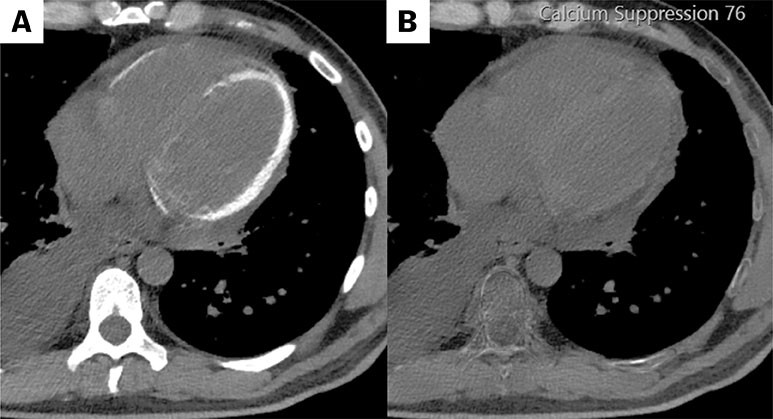

CT-bildene er fra en undersøkelse med opptak uten intravenøs kontrast. Bildet til venstre viser høy attenuasjon i myokard i venstre ventrikkel, og i mindre grad i høyre ventrikkel. Attenuasjonen er tilnærmet lik skjelett i bildet, og tettheten kan passe med forkalkninger.

Opptaket er gjort på en spektral-CT, som har økt mulighet for å differensiere mellom ulike vevstyper. Maskinen utnytter de ulike energinivåene i røntgenstrålen, og den kan skille mellom grunnstoffer som jod og kalk utfra absorpsjonsnivået, da begge gir høy attenuasjon. Kalksuppresjon, vist på bildet til høyre (B), bekrefter at høyattenuasjonen i bildet til venstre (A) skyldes tilstedeværelsen av kalk i vevet.

Bildene er av en mann i 40-årene med kostregulert diabetes og uten kjent kronisk nyre- eller hjertesykdom. Fire uker før de aktuelle bildene ble tatt, ble han innlagt med E. coli-sepsis med multiorgansvikt og intensivbehandling med hemodialyse. Indikasjonen for CT thorax var betydelig pleuraeffusjon, og funnet av forkalkninger i myokard var overraskende. Tre uker senere viste ekkokardiografi betydelig økt ekkogenisitet i myokard, unntatt i septum (se video). Myokardet kontraherte, men ejeksjonsfraksjonen var redusert, mest longitudinelt, og den ble estimert til rundt 40 %.

CT- og ekkofunnene passer med diffust kalknedslag i myokard. Tilstanden er beskrevet i noen kasuistikker, og kan oppstå ved forstyrrelse i kalsium- og fosforbalansen, kronisk nyresvikt eller som her, ved inflammatorisk skade av myokard etter sepsis med nyresvikt (1). Tilstanden gir økt risiko for hjertesvikt, og oppfølging av hjertefunksjonen er indisert. (2). Målrettet behandling for å redusere forkalkningene finnes så langt ikke, men i en annen kasuistikk er det beskrevet spontan regress (3).